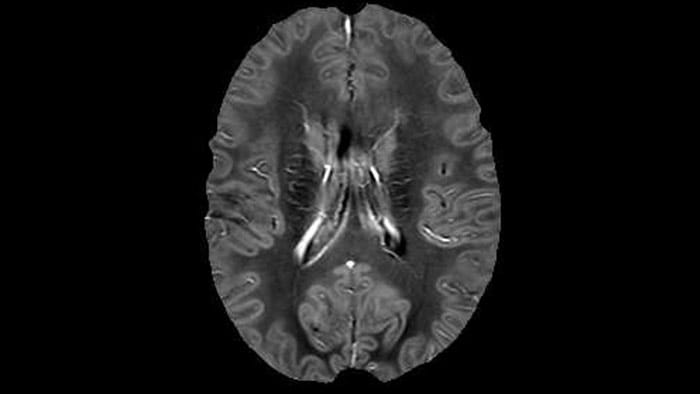

QSM elition Kames algorithm

QSM based on a Compressed SENSE multi-echo SWI.

Dr. Rauscher says, “With better gradients we can use a shorter echo spacing on the spin echo, so we get better sampling of the rapidly decaying myelin signal, which typically has T2 of around 10-20 milliseconds at 3 Tesla. If we can reduce echo spacing from about 8 to 5-6 milliseconds, we get a much better sampling of the short decay component and increase our SNR, which is a big advantage. The same is true for multi-echo gradient echo which we use for susceptibility mapping and for mapping venous vessels in MS.”

For instance, we can get the combined information from looking at advanced diffusion, multi-shell diffusion combined with myelin water, and then also add quantitative susceptibility mapping and get a better idea of tissue micro structure effects from all three combined. On the old scanner we only had time to run maybe one or two of these sequences in addition to the conventional scans,” says Dr. Rauscher.